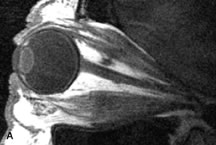

Extraocular muscle enlargement in patients with thyroid-associated orbitopathy is demonstrated equally well with CT and MRI studies. However, the superior tissue contrast on MR images reveals better details of the relationships of the optic nerve to the thickened muscles at the orbital apex (Fig. 16).50 In addition, MRI may be able to differentiate between muscles that are enlarged as a result of edema and active inflammation and those enlarged because of fibrosis by their T2 relaxation times.21 Quantitative MRI was not found to be accurate in predicting the success of low-dose orbital irradiation.51 However, a muscular index relating the diameters of the rectus muscles to the bony orbital dimensions was useful in predicting optic nerve compression.52

Fig. 16. A-C, T1-weighted MR scans obtained with a high-resolution surface coil demonstrate fusiform enlargement of the extraocular muscles. The medial, lateral, and inferior rectus muscles are especially involved. Note the relative sparing of the tendinous insertions, a finding characteristic of this disease process, as well as fatty infiltration of the lateral and inferior rectus muscles. There is marked proptosis, best visualized on the sagittal image (A), and mild crowding of the optic nerve at the orbital apex.